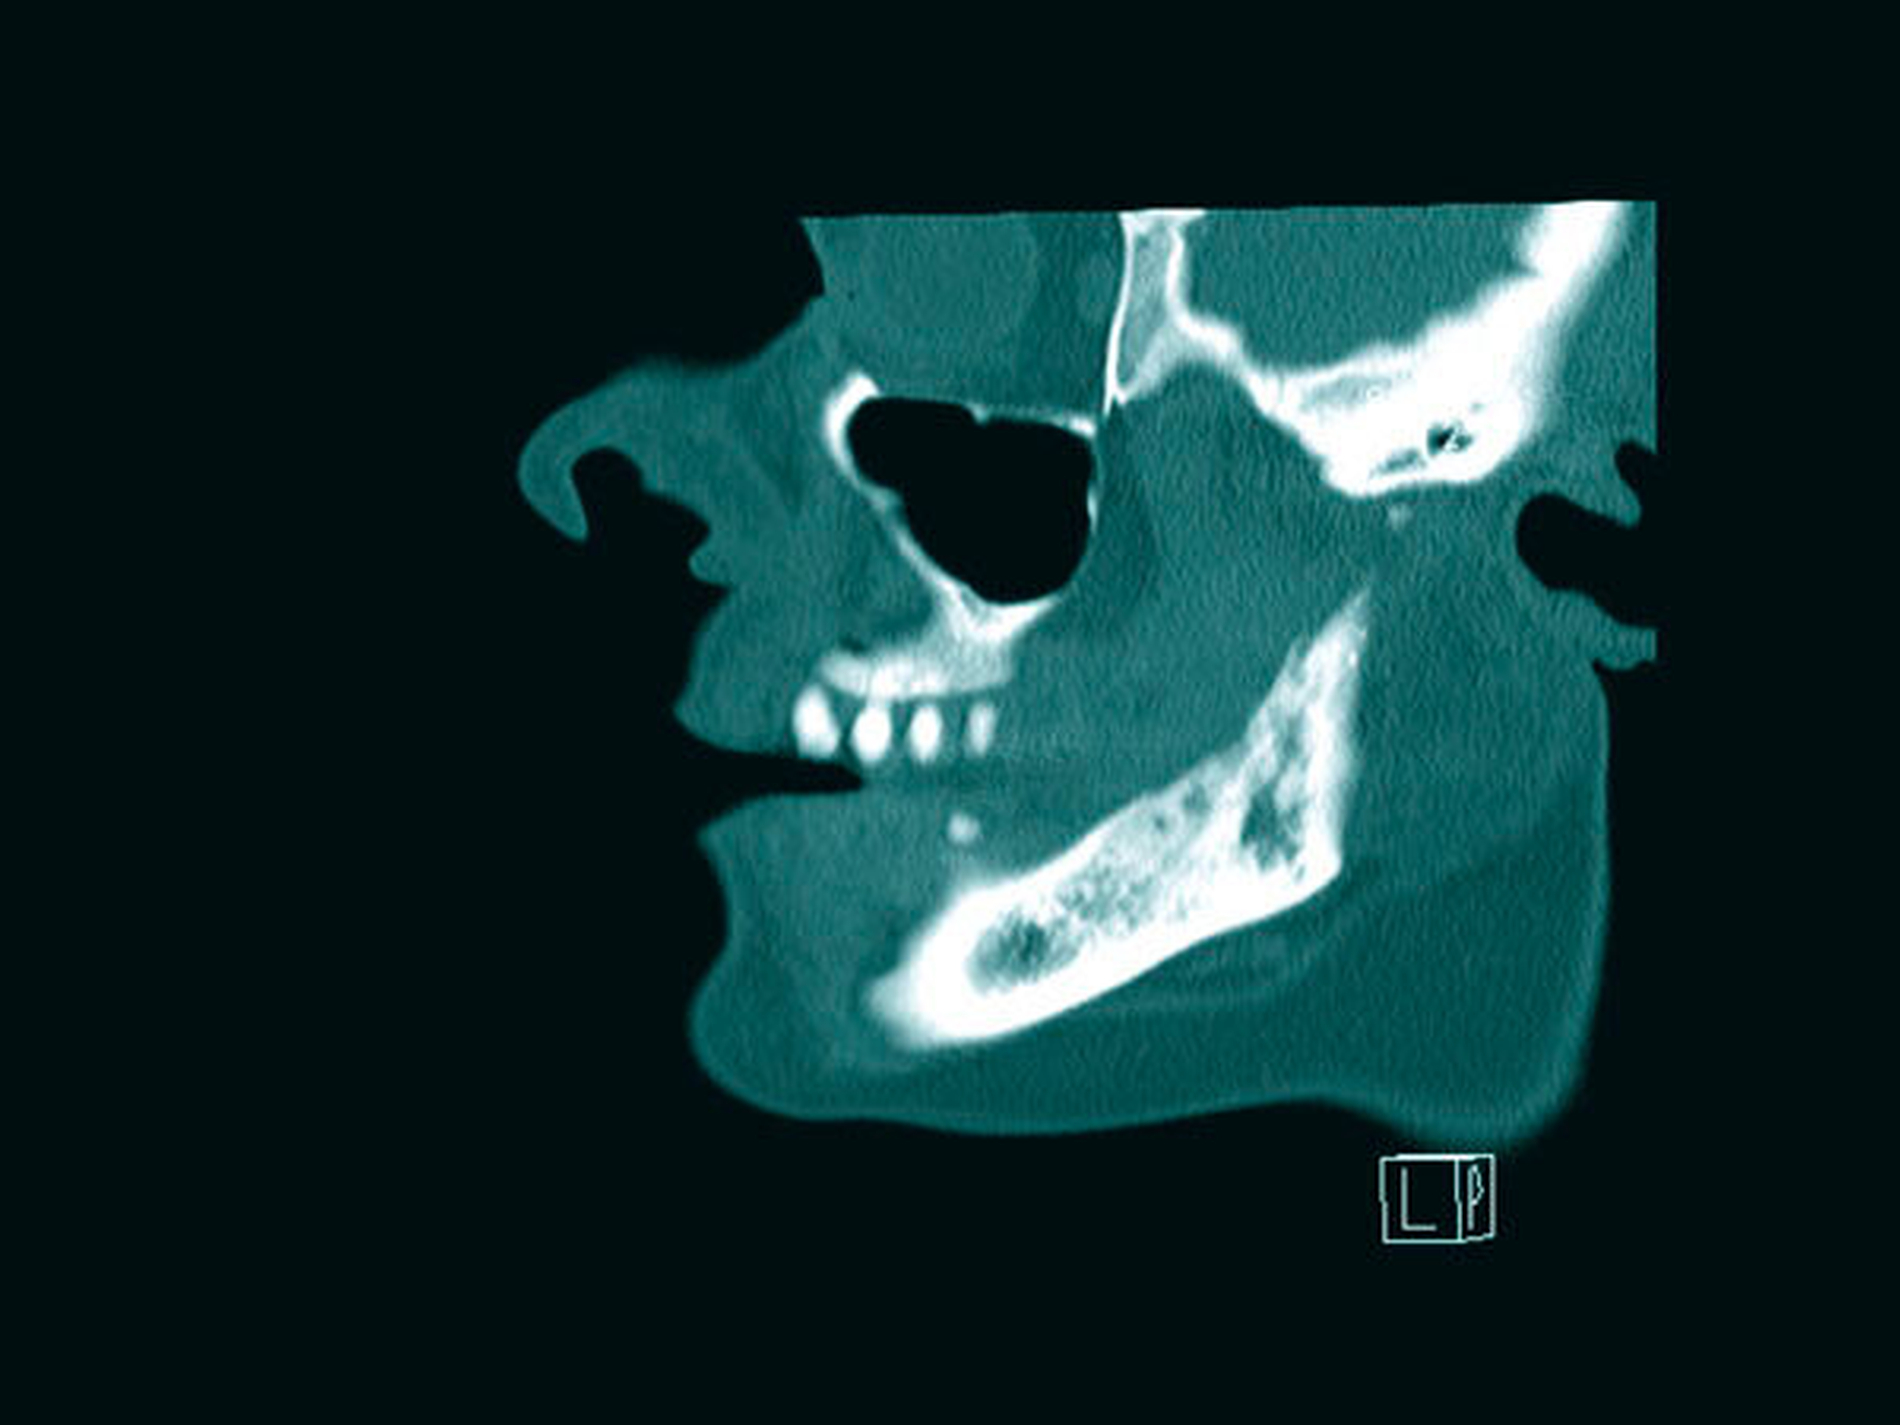

Aufgrund einer erneuten starken Zunahme der Beschwerden 2018 war der Leidensdruck der Patientin nach drei Jahren nun so groß, dass sie nach Bestätigung der erneuten Aktivitätszunahmen im Bereich des Capitulums in der Knochenszintigrafie und einer erneuten Osteolyse und in der CT im Bereich des aufsteigenden Unterkieferastes rechts und des Capitulums die Planung eines total-endoprothetischen Kiefergelenkersatzes wünschte (Abbildungen 8a bis 8c).